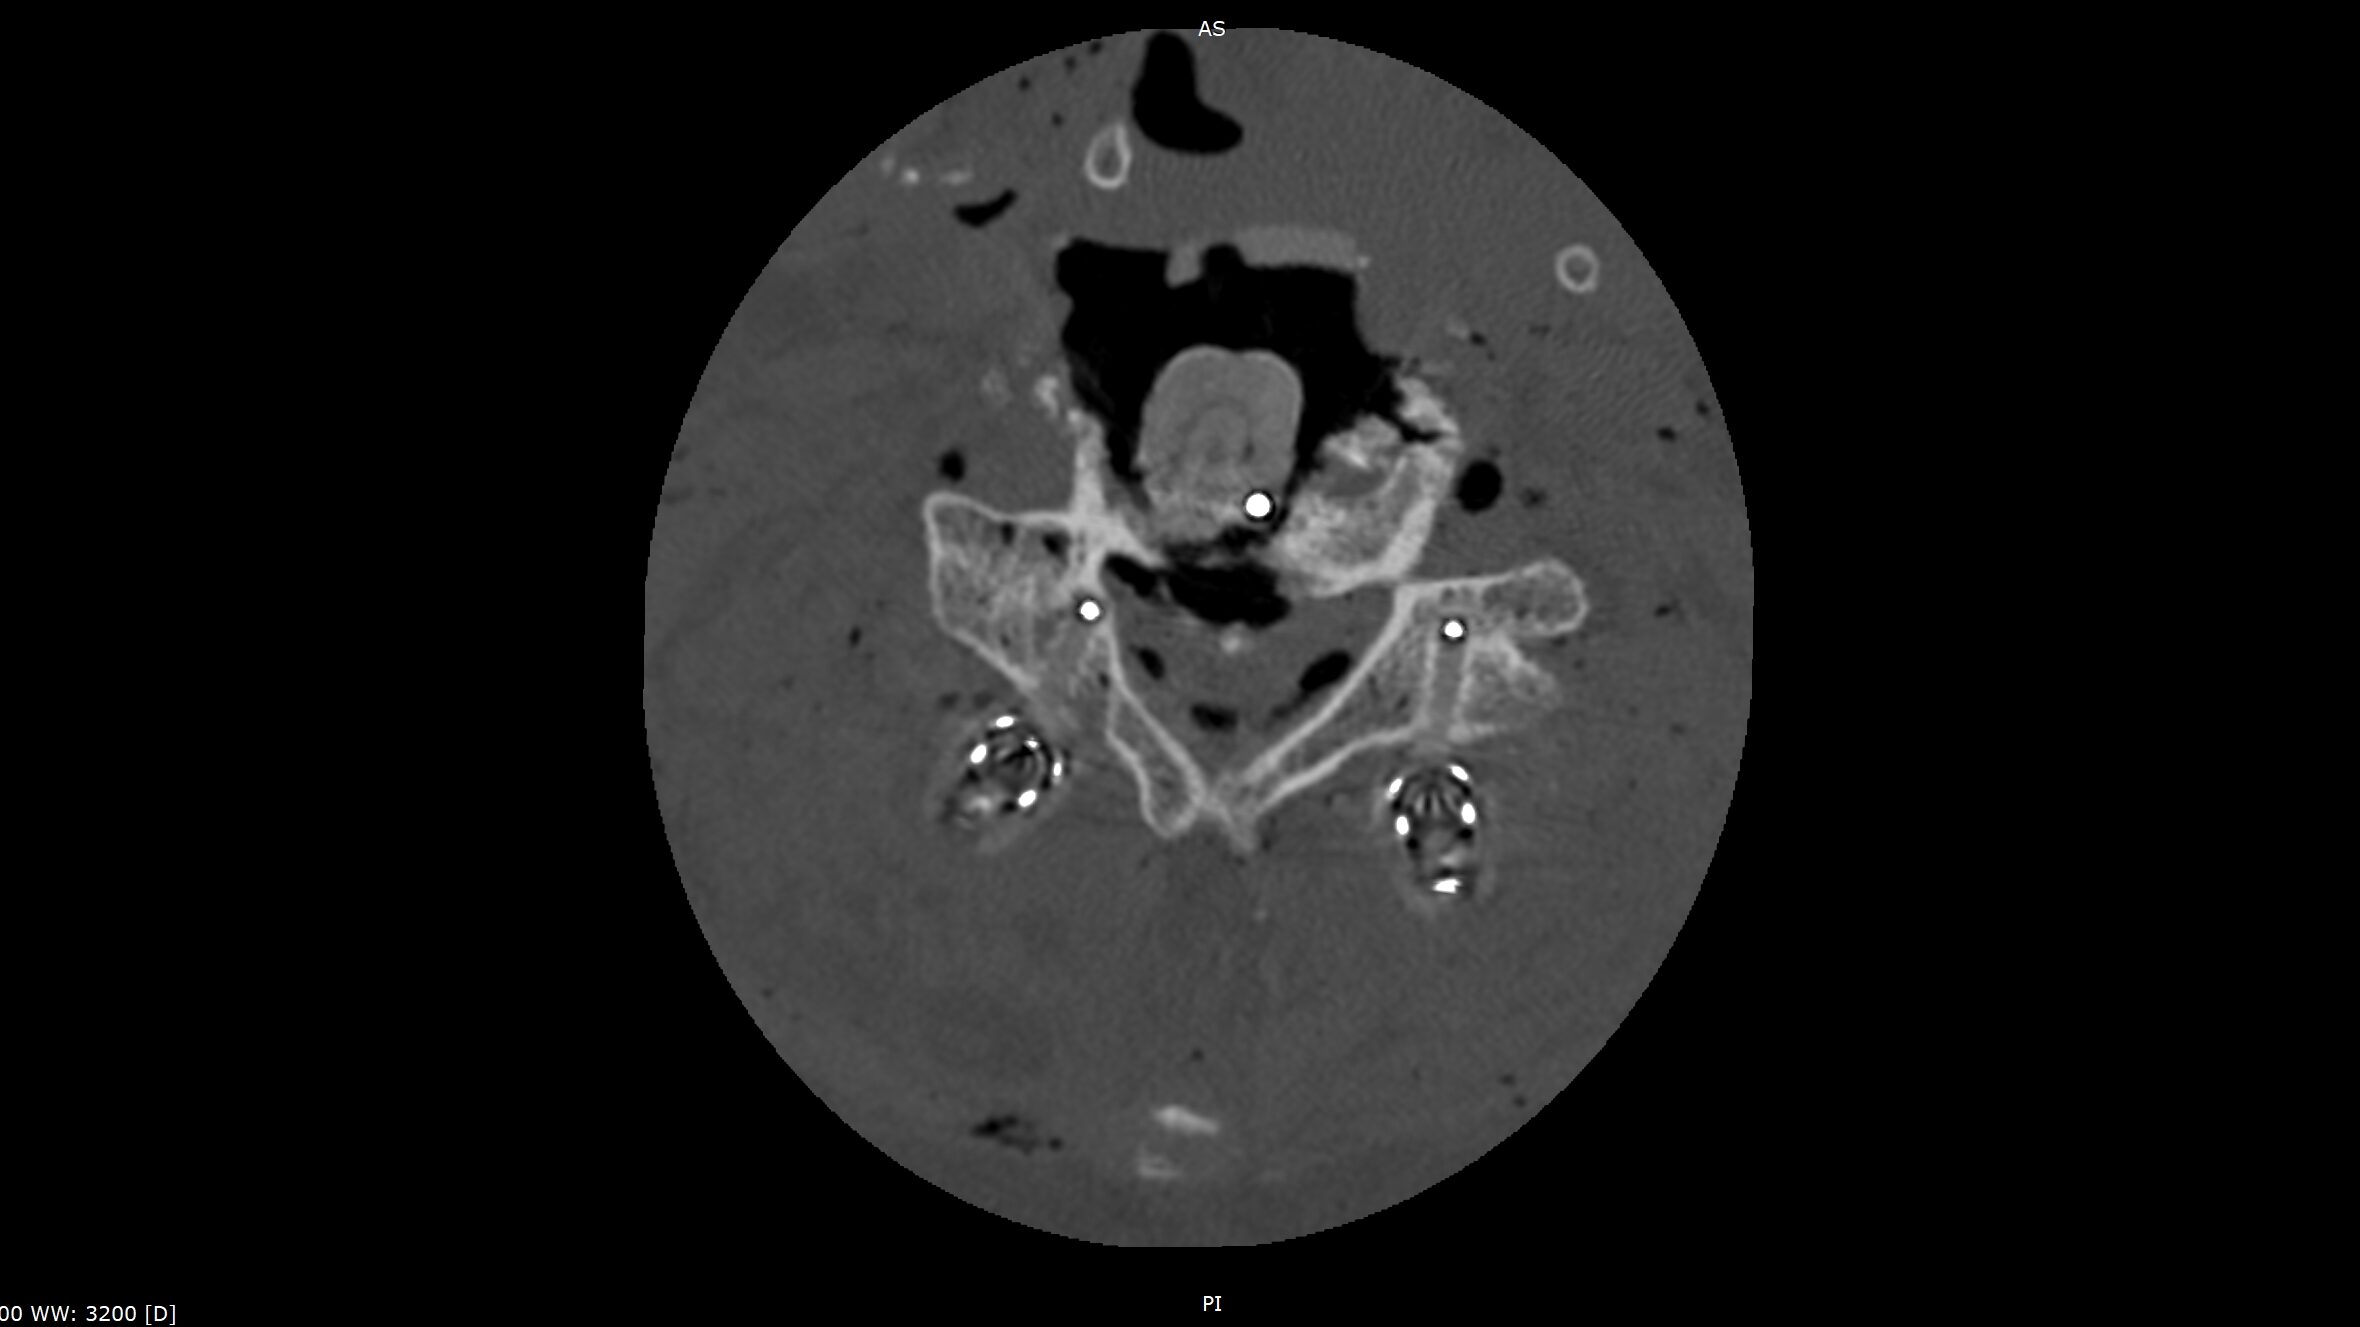

The CMORE® Cervicothoracic (CT) System is an enhanced set of instruments and implants for posterior stabilization of the cervicothoracic spine. The world’s first spinal implants made of nonmetallic and radiolucent BlackArmor® technology now enable a full spectrum of treatment modalities in adjuvant tumor therapy and enhance postoperative imaging diagnostics in the cervicothoracic spine.

- BlackArmor® material is radiolucent in all diagnostic imaging modes and facilitates adjuvant radiation treatment

- The first tulip made of BlackArmor® material for artifact-free CT and MRI imaging